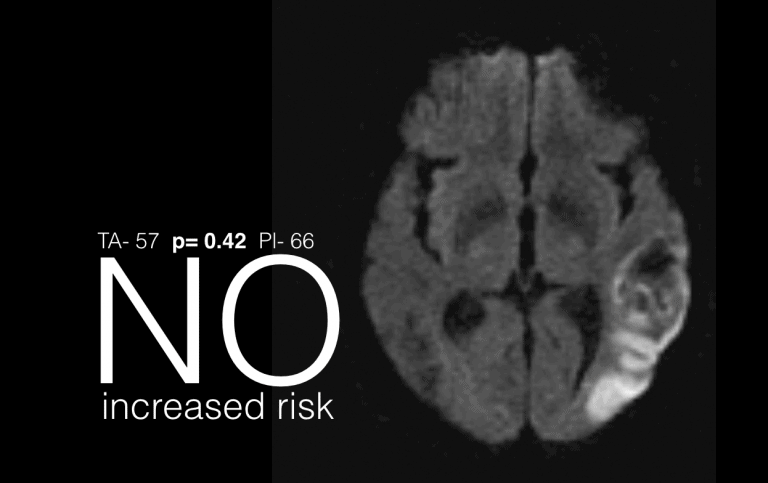

Data slides must be easily interpreted, memorable and clear. They will support the message, not distract, cannot be taken directly from a scientific document and are best if their theme,…

Data slides (2)

In the previous post on data slides it was highlighted that “Data slides must be easily interpreted, memorable and clear. Few are. Most could be improved.” A data slide in…